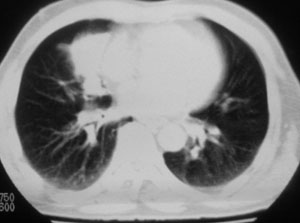

性别 男  62岁 因咳嗽及左肱骨剧烈痛疼数天来院检查。

右中央型肺癌并肱骨转移。

考虑右肺中叶肺癌并左肱骨转移伴病理性骨折。

支持右肺中心型肺癌并肺内及左肱骨转移伴病理性骨折

右肺中心型肺癌并中叶不张,左肱骨溶骨性转移并病理骨折。